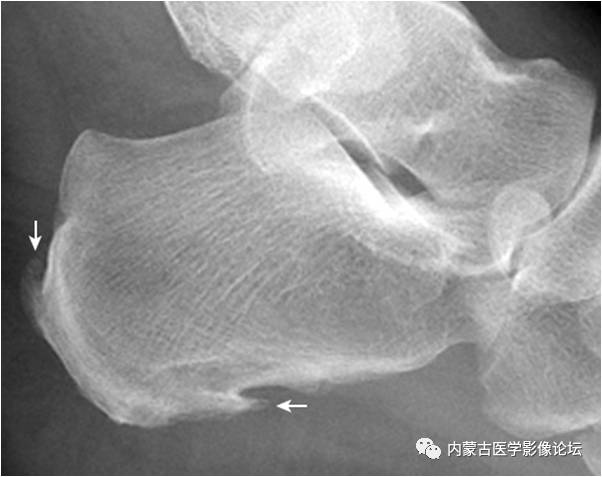

2.Haglund外生骨疣与不典型骨刺:跟骨后上缘骨刺样突起(箭),属正常变异,称Haglund外生骨疣。穿高跟鞋时可损伤相邻的跟腱,形成Haglund综合征;跟骨结节下缘前突骨刺样突起(箭头),正常人可见,可无临床症状。